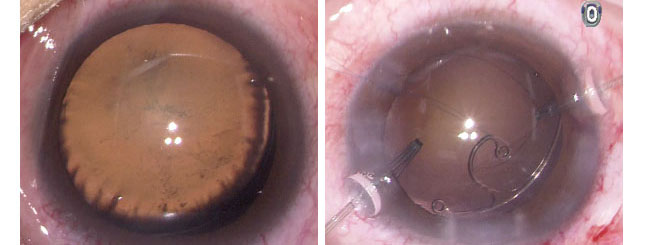

創傷性白內障亦會較大機會出現晶體移位及不能順利植入晶片的可能。有時亦需同時植入囊張力環/節(capsular tension ring/ segment) 以穩定人工晶體的後置。

(醫生病例) 創傷性白內障晶體移位(左圖)

(醫生病例) 白內障手術中植入囊張力節以矯正晶體囊移位(右圖)